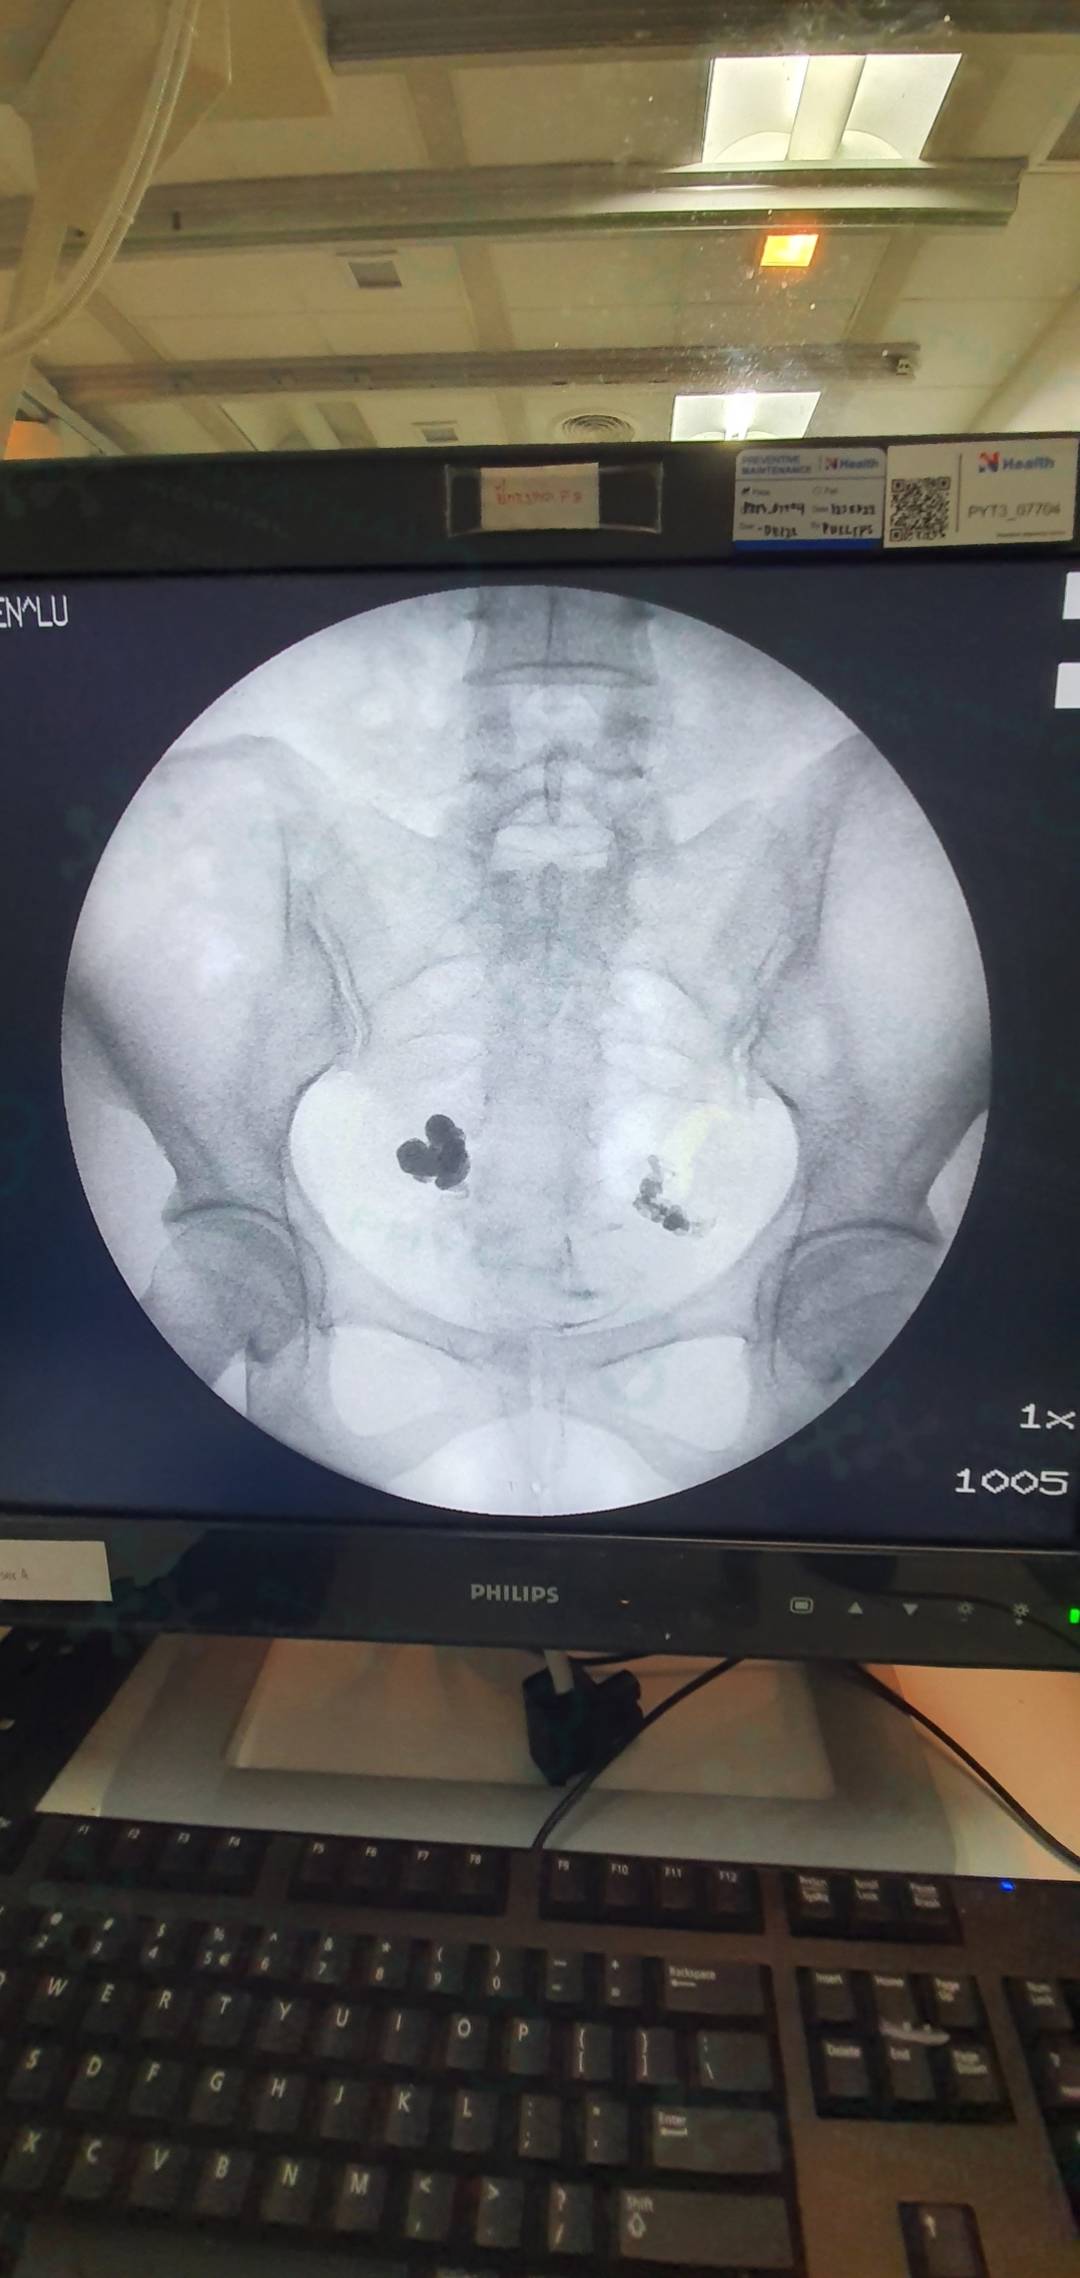

泰国试管婴儿问题:输卵管积水还能做试管婴儿吗?

输卵管积水会影响到试管婴儿的成功率。对于年龄大、卵巢功能欠佳的患者,就算是较轻的输卵管积水,医生建议还是先取卵,培育好胚胎以后再治疗输卵管积水,等治疗好以后再移植。因为卵巢随着年龄的增大会逐渐衰退,卵子的数量就会减少。如果治疗输卵管积水耽误了最佳的进入疗程时间,那就得不偿失了。所以可以先取卵配胚胎并冷冻胚胎,等处理完积水后再行冷冻胚胎复苏移植。所以输卵管积水的患者,只要操作正确还是能做试管婴儿的哈。